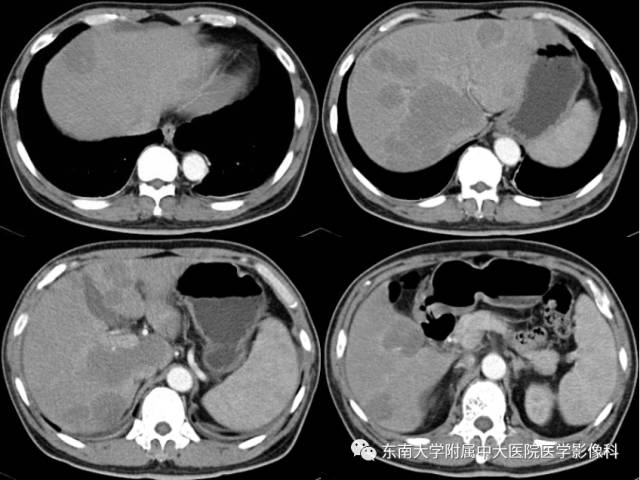

男,53岁,因“反复发热12天”入院。

实验室检查:血细胞分析:白细胞计数 2.75×10^9/L↓,血红蛋白 121g/L↓,血小板计数 101×10^9/L↓,超敏C反应蛋白 15.5mg/L↑;纤溶功能检查:凝血酶时间 17.3秒↑,抗凝血酶 134%↑,纤维蛋白原降解产物 8.61mg/L↑,D-dimer 798ug/L↑;肿瘤标志物:糖类抗原199 101.1U/mL↑,神经元特异性烯醇化酶 18.77ng/mL↑,细胞角质蛋白19片段 3.85ng/ml↑;肝生化:谷丙转氨酶 809IU/L↑,谷草转氨酶 717IU/L↑,碱性磷酸酶 405IU/L↑,γ-谷氨酰转肽酶 401IU/L↑,乳酸脱氢酶 909IU/L↑;

2017-08-11 腹部CT增强

2017-09-01 腹部CT增强 复查